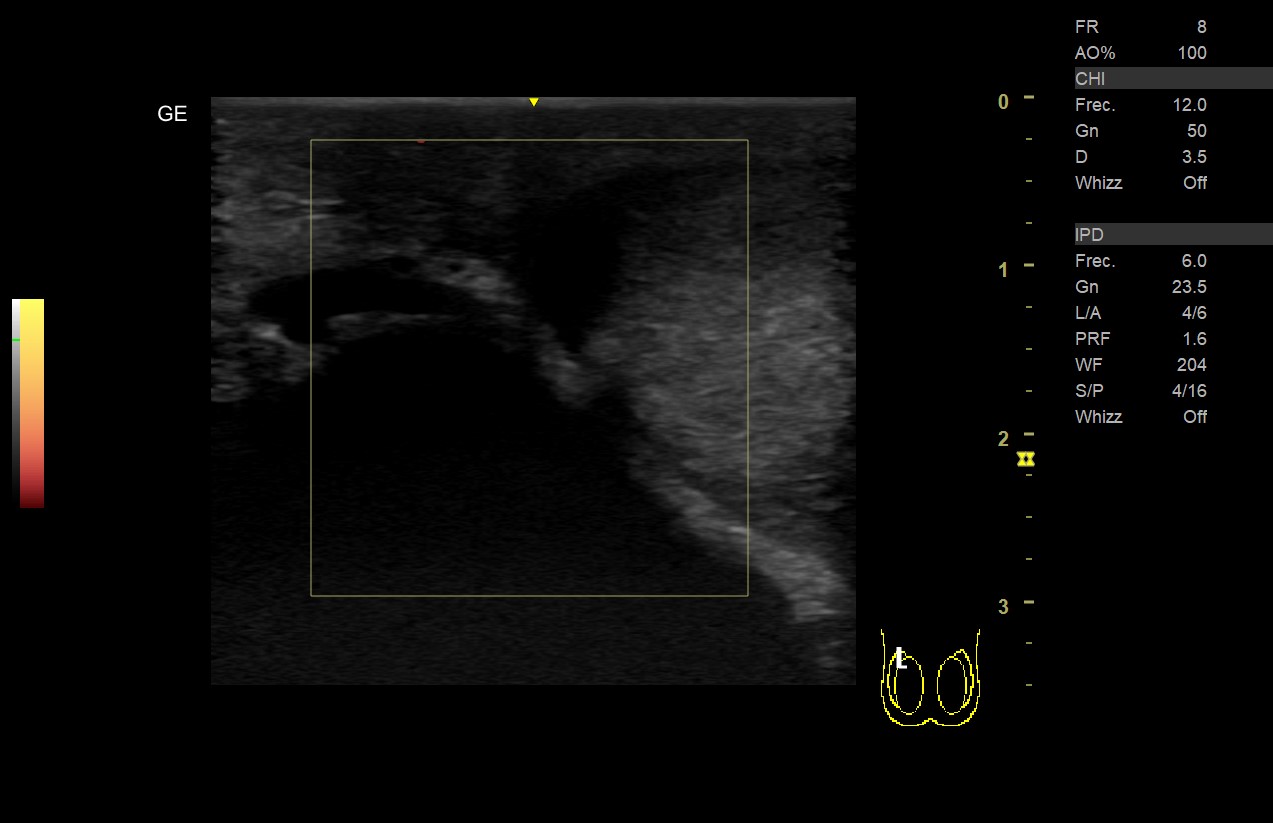

• Teste derecho: aumento de volumen con ecogenicidad heterogénea (áreas más hipoecogenicas), sin captación Doppler color ni power en teste o epidídimo derecho y presencia de líquido en bolsa escrotal.

• Teste izquierdo: volumen y ecogenicidad homogénea con captación Doppler en teste y epidídimo, ausencia de hidrocele.